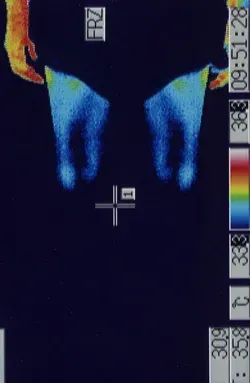

突発性難聴の治療で高圧酸素室に入って治療をした時、耳ぬきがうまくいかずに滲出性中耳炎になってしまいました。痛みは無いので鼓膜に穴をあけるのもとても不安です。滲出性中耳炎は、鍼治療でよくなりますか?

内耳のリンパの流れを良くすることで改善することが多いです。

滲出性中耳炎は、痛みが無いので癖になってしまうことが多いのですが、比較的、鍼治療が効果的です。お医者様は、鼓膜にチューブを入れることがあるのですが、鼓膜の中に落ち込んでしまうこともあるので、鍼治療をされる方も多いです。不安や恐怖が多いほど、症状が改善しなくなることが多いので、ストレスをためないようにしましょう。

詳しくは、 滲出性中耳炎の鍼治療 をご覧ください。